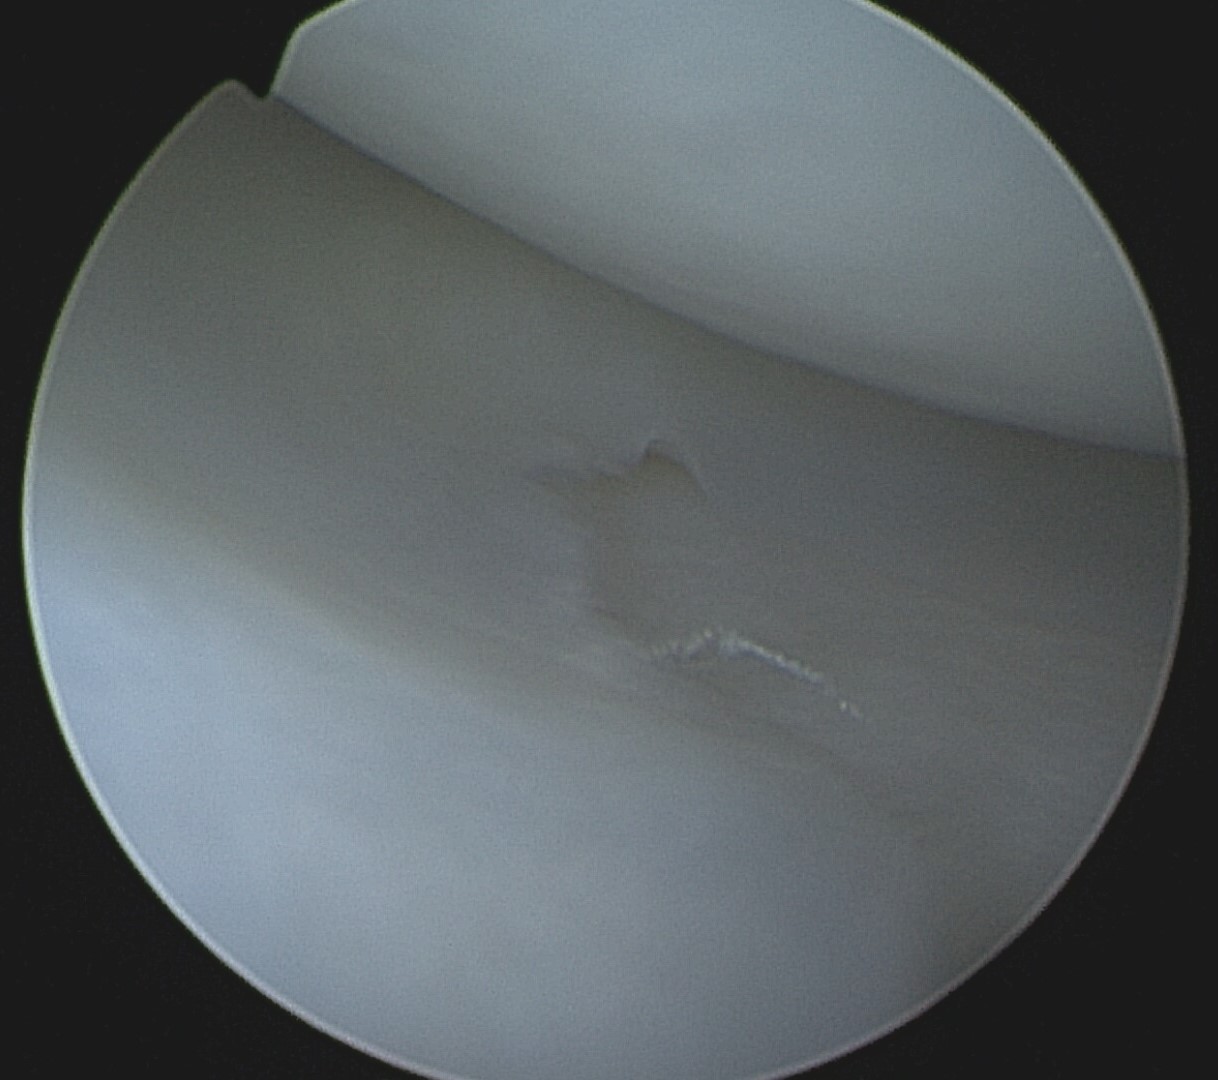

Torn Dog Meniscus

A torn meniscus in dogs is typically characterized by the back portion of the meniscus displacing forward between the femur and tibia. This can sometimes (rarely) be heard by owners as a clicking or popping sound, referred to as a meniscal click. In the arthroscopic video below, veterinary surgeon Dr. Sam Franklin demonstrates a dog meniscus tear where the meniscus displaces forward repeatedly when the tibia moves due to the CCL rupture. The video illustrates how pushing the torn meniscus back into place won’t resolve the issue. This torn portion of meniscus needs to be removed or, in rare cases, repaired.

In many cases the torn meniscus become permanently wedged between the femur and the tibia as shown in the image below top, right. This is an arthroscopic image of a whole back half of a medial canine meniscus that is torn and displaced forward sitting between the femur and tibia, similar to the video on the left. This is referred to as a peripheral detachment and the dog’s torn meniscus needs to be removed.